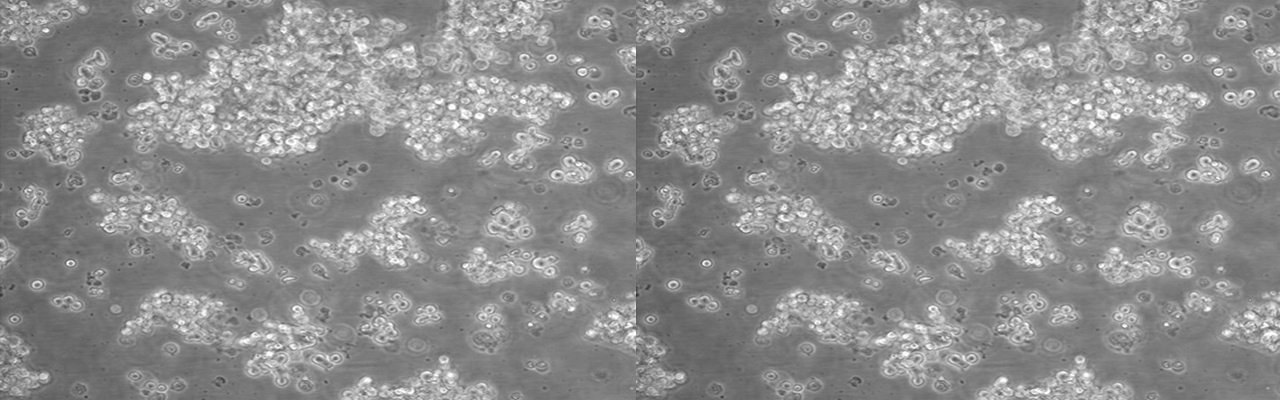

| 名称 | NCI-H69 |

| 细胞全名 | 人小细胞肺癌细胞 |

| 生长特性: | 悬浮生长 |